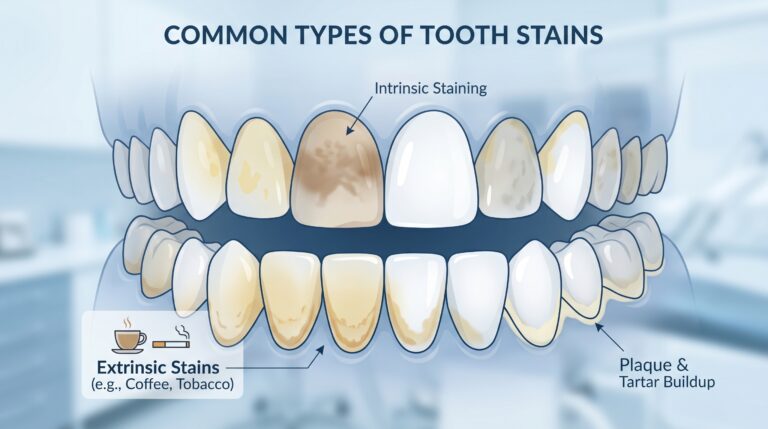

Manchas en los dientes: causas, tipos y cómo eliminarlas eficazmente

Las manchas en los dientes son uno de los problemas más visibles dentro de la salud bucodental. Aunque muchas veces se asocian únicamente con la estética, en algunos casos también pueden ser una señal de problemas más profundos. Si quieres entender el contexto general en el que aparecen, te recomiendo revisar la guía completa sobre…